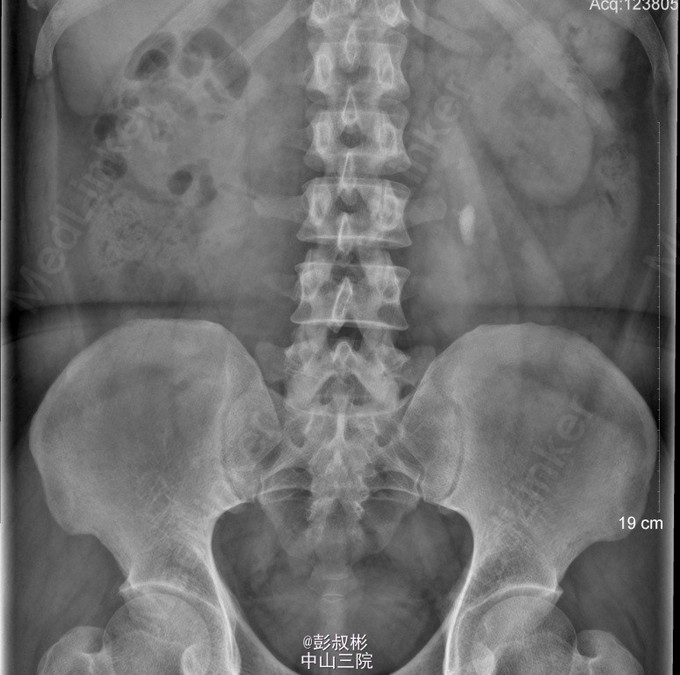

男性,37岁,体检发现左输尿管结石2月。泌尿系彩超:左输尿管上段结石并左肾积液。腹部平片:左输尿管上段结石。腹部CT:左输尿管上段结石,大小约18×12×9mm,左输尿管上段及左肾盂积水,左肾功能减退。